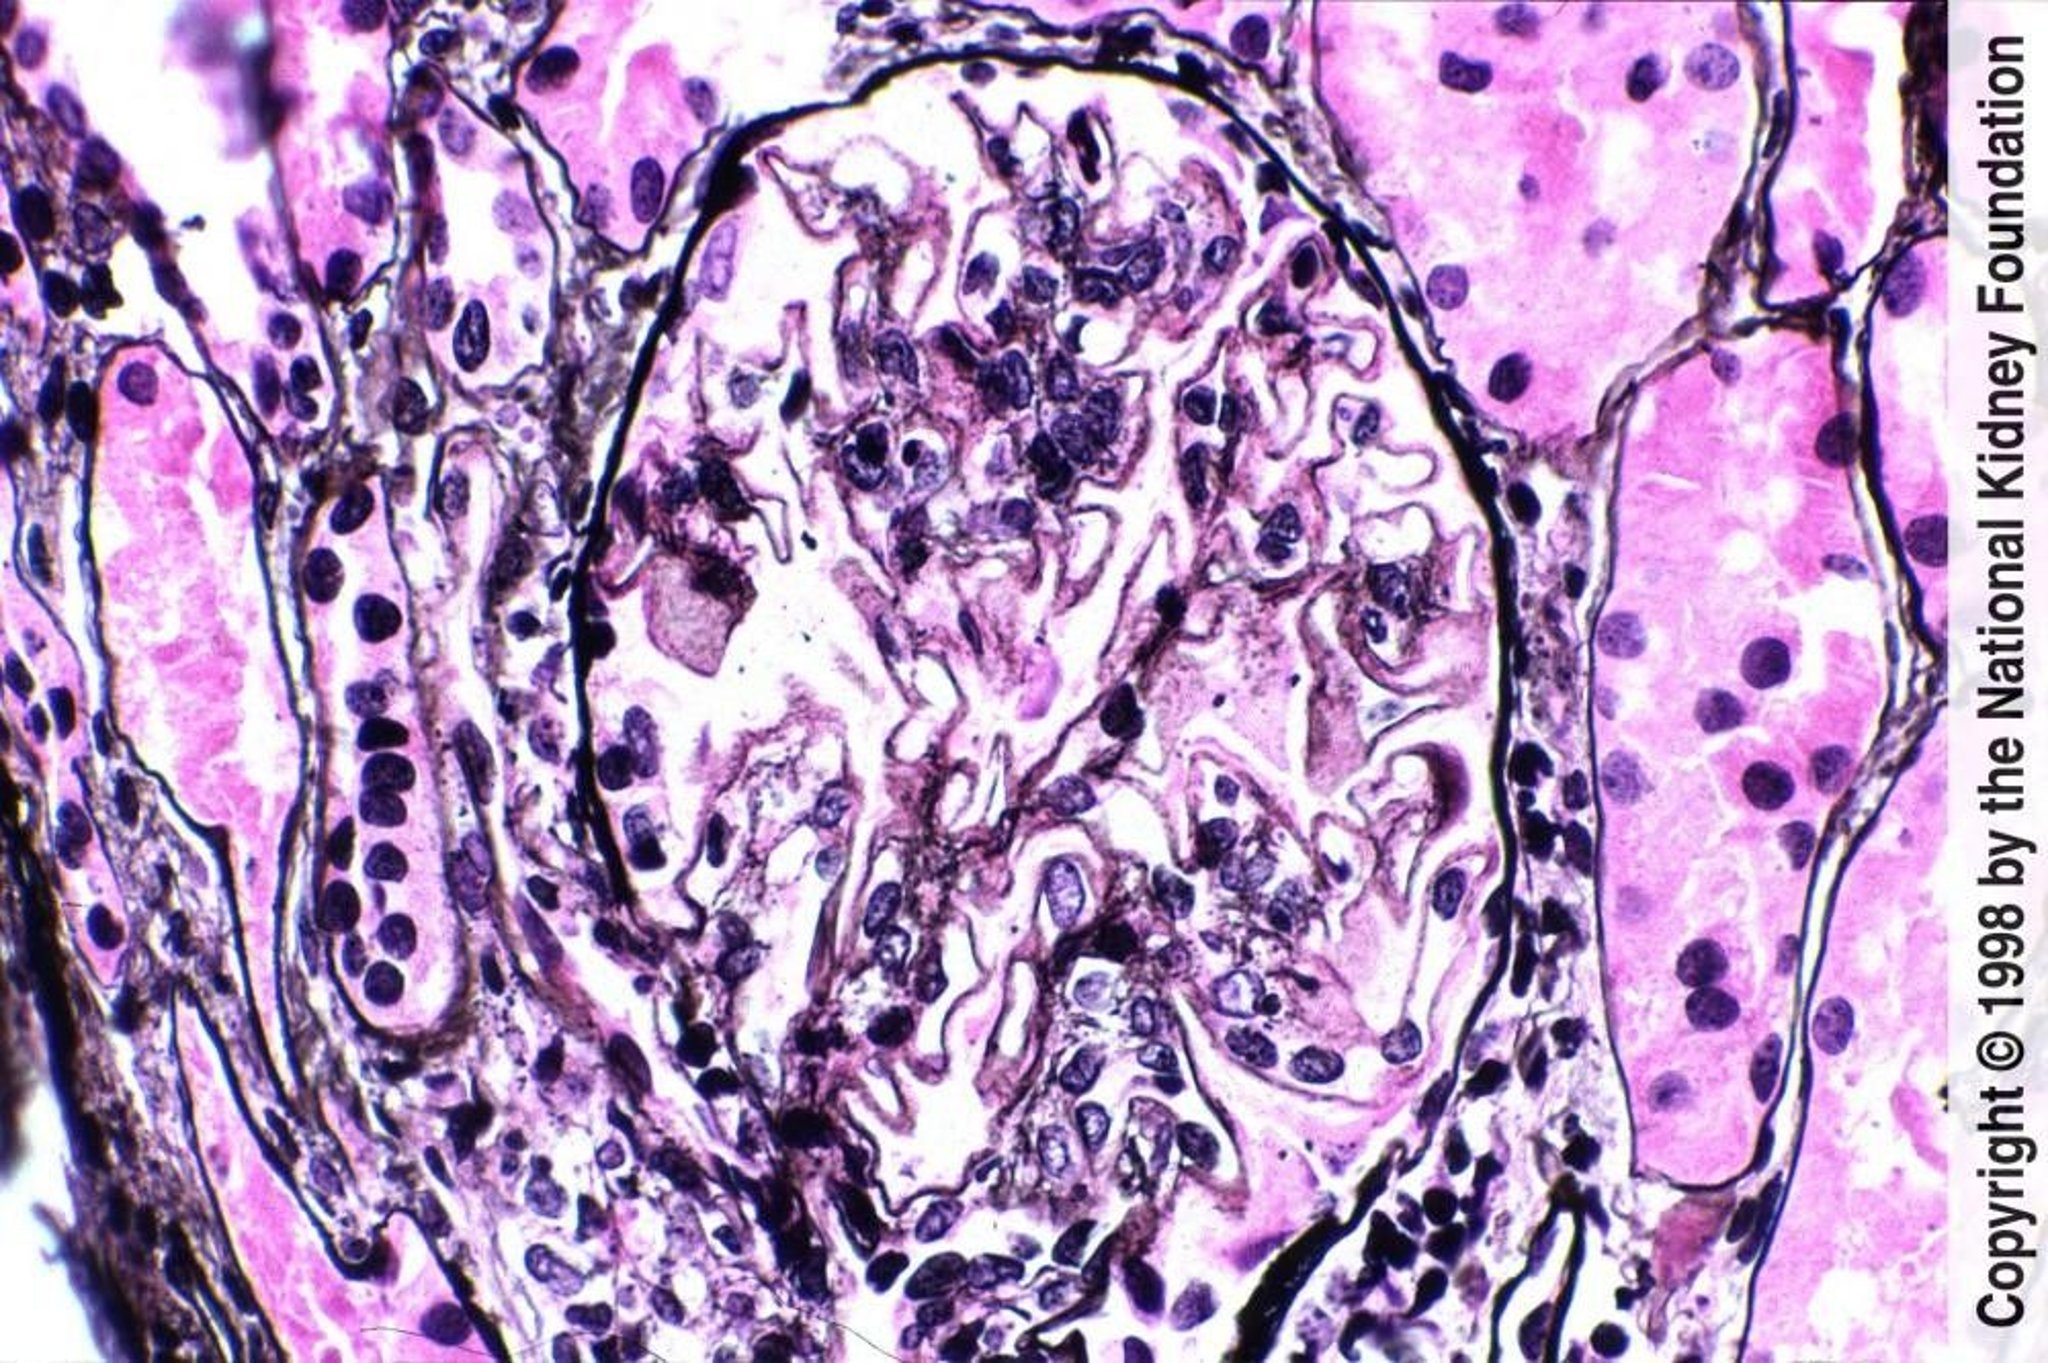

Lupus Nephritis—Membranous (Class V)

Diffuse holes, small spikes, and mild mesangial expansion with small areas of pink staining indicate mesangial immune complex deposits (Jones silver stain, ×400).

Image provided by Agnes Fogo, MD, and the American Journal of Kidney Diseases' Atlas of Renal Pathology (see www.ajkd.org).